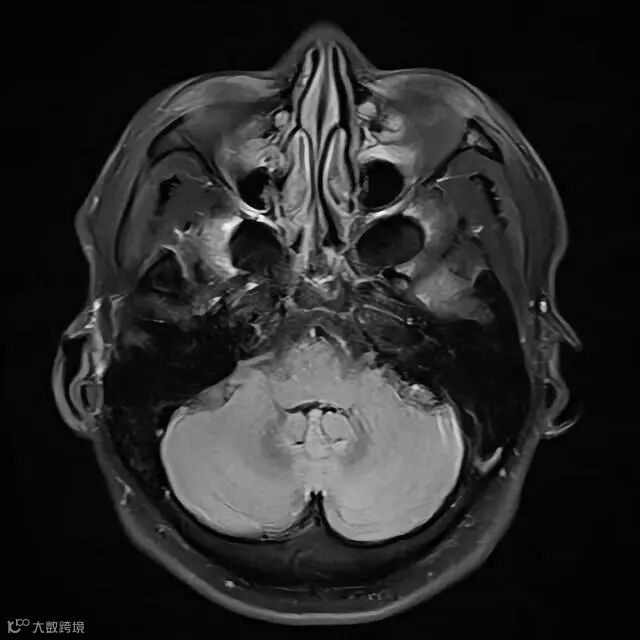

头部——MRI最佳,CT次之

用CT扫描颅底部时,该部位的骨结构会出现各种伪影,直接影响到对后颅凹脑组织的观察。

MRI筛查则无此类骨伪影干扰,能使后颅凹的解剖结构和病变观察更清晰。由于头部血管的分布广泛,无创了解其变窄、畸形等无感觉的中风潜在风险,用MRI来检查效果最佳。